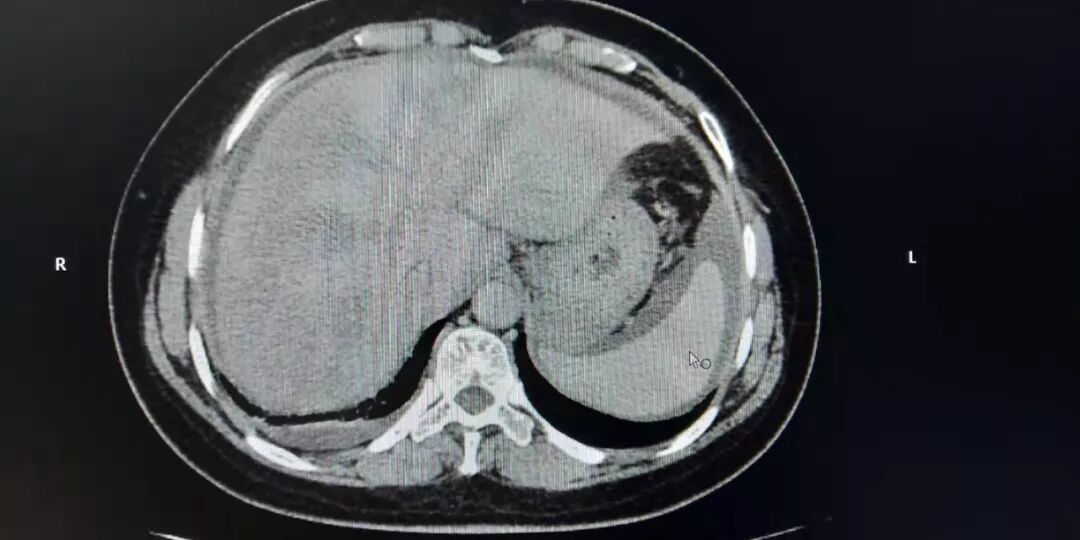

根据患者临床检查和病史,在排除肝前肝后型门脉高压后,内科团队确定患者为肝性门脉高压。同时排除常见的先天遗传及后天获得的如:病毒性肝炎、自身免疫性肝病等原因引起的肝硬化。结合增强CT典型的肝脏不均匀的灌注,呈典型的花斑样改变,同时有大量服用中草药长达一年的病史,由肝小静脉闭塞症所致的门脉高压症,诊断基本成立。